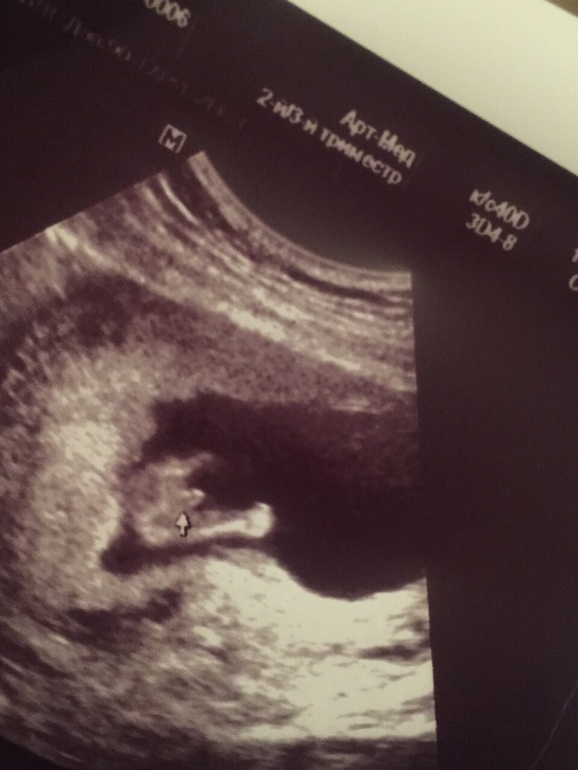

Это точно мальчик?

Это 14 нед , первый раз когда пол сказали , просто удобный ракурс и не более , всё по нормам)

А это у вас какой срок? У меня в таком ракурсе стручок был по короче, а мошонка как бы пополам была поделена